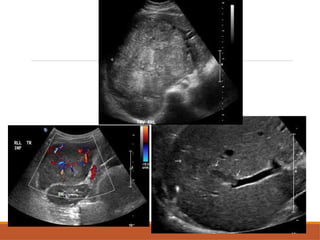

USG  Variable inappearance. usually hypoechoic. A thin ,peripheral hypoechoic halo( fibrous capsule). Larger tumors often are heterogeneous (necrosis,hge & fibrosis). May invade the portal & hepatic veins. Most tumor will show central vascularity on Doppler study.

CT SCAN NECT: largehypodense mass, often with central area of low attenuation(necrosis). May be isodense to liver. CECT: non necrotic area enhances strongly in arterial phase & early washout in subsequent phases. Detection of venous invasion (portal,hepatic veins,IVC).

• #29 These are the grey scale usg image showing illldefined heterogeneously isoeceic lesion noted in segment 6 and 7 of right lobe with peripheral hypoeceic rim suggesting fibrous capsule On doppelr study there is asignificant internal vascularity within the lesion Another image of hcc showing invasion of tumoir into the right brmach of the portal vein

• #31 Axial cect images of hcc in segment 4a in showing enhancement odf elsion in arterial phase and washout of tumour in portal venous phase and delayed phases So early washout of the contrast suggestive of hcc